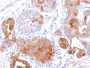

This antibody recognizes a protein of 15 kDa, identified as Gross cystic disease fluid protein 15 (GCDFP-15). It is a major protein component of benign breast gross cysts. It is a known marker of breast cancer, as it is found in approximately 50% of all breast cancer specimens. GCDFP-15, also known as PIP, for prolactin inducible protein, is a prolactin and androgen controlled protein. This antibody is useful in the identification of metastatic breast carcinoma, or fluid analysis.Primary antibodies are available purified, or with a selection of fluorescent CF® Dyes and other labels. CF® Dyes offer exceptional brightness and photostability. Note: Conjugates of blue fluorescent dyes like CF®405S and CF®405M are not recommended for detecting low abundance targets, because blue dyes have lower fluorescence and can give higher non-specific background than other dye colors.

Positive Control

HepG2 Cells. Breast or Pancreas.

Higher concentration may be required for direct detection using primary antibody conjugates than for indirect detection with secondary antibody|Immunofluorescence: 0.5-1 ug/mL|Immunohistology (formalin): 0.5-1 ug/mL|Staining of formalin-fixed tissues is enhanced by boiling tissue sections in 10 mM Tris buffer with1 mM EDTA|Flow Cytometry 0.5-1 ug/million cells/0.1 mL|Western blotting 0.5-1 ug/mL|Optimal dilution for a specific application should be determined by user